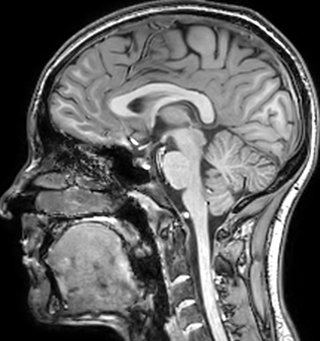

of limiting MWI to the brain, even without the cerebellum, we can now spend about the same amount of time and scan the whole brain and the cervical spinal cord, which is a huge boost for us.” Dr. Rauscher says, “For MWI we perform 3D T2 with 32 or more echoes. This used to take a long time, but with Compressed SENSE we can decrease this to ten minutes for the whole head. Because of the large field of view (FOV) on the readout direction, we even get information from the brainstem, which we previously missed when we were using the GRASE approach. Having the whole head scan is nice because it has spatial resolution, orientation and FOV that are comparable to the standard 3D clinical MS scans, including the FLAIR and 3D T2, and a 3D T1 for brain volume.”

The techniques for measuring myelin have changed a lot over the years. “Since we are using the Elition, our myelin water images are much better. We're now acquiring 1 x 2 x 5 mm voxels and displaying at 1 x 1 x 2.5 mm. For a whole brain we can now measure the fraction of water in the myelin component in only about five or six minutes,” Dr. MacKay says.

According to Dr. MacKay, MWI images benefit from Elition’s high quality gradients. “We need good gradients because we want to be able to do multi-echo sequences that have short TE times.”

Dr. Rauscher says, “With better gradients we can use a shorter echo spacing on the spin echo, so we get better sampling of the rapidly decaying myelin signal, which typically has T2 of around 10-20 milliseconds at 3 Tesla. If we can reduce echo spacing from about 8 to 5-6 milliseconds, we get a much better sampling of the short decay component and increase our SNR, which is a big advantage. The same is true for multi-echo gradient echo which we use for susceptibility mapping and for mapping venous vessels in MS.”